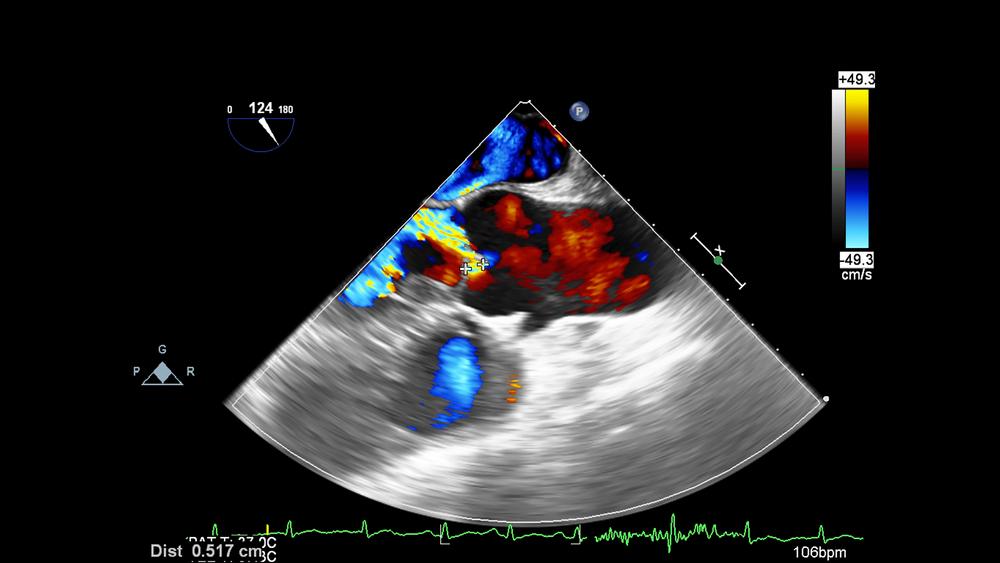

Siêu âm Doppler là một kỹ thuật không xâm lấn dùng để ước tính lưu lượng máu qua các động mạch và tĩnh mạch chính. Phương pháp này còn giúp ước tính tốc độ chảy của máu bằng cách đo tốc độ thay đổi tần số sóng siêu âm.

Cụ thể, trong quá trình siêu âm Doppler, một thiết bị cầm tay (gọi là bộ chuyển đổi) được lăn nhẹ qua da bụng mẹ bầu. Thiết bị này dùng để gửi và nhận các sóng âm thanh được khuếch đại qua micrô. Các sóng âm thanh tần số cao (siêu âm) dội lại từ các vật thể rắn, bao gồm cả các tế bào hồng cầu đang lưu thông. Sự di chuyển của các tế bào máu tạo ra sự thay đổi cao độ của sóng âm phản xạ. Đây gọi là hiệu ứng Doppler. Nếu máu không chảy, cao độ không thay đổi. Kết quả được hiển thị trên màn hình máy tính dưới dạng đường, gọi là dạng sóng.

So với siêu âm thông thường dùng sóng âm thanh để tạo ra hình ảnh, siêu âm Doppler có ưu điểm nổi bật là hiển thị được lưu lượng máu trong cơ thể.